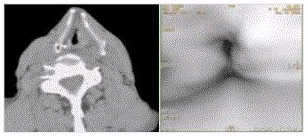

- [材料题] 男性,60岁。声音嘶哑半年,CT表现见下图。

- 简答题1、该患者诊断为?

- 简答题2、请问咽腔可以划分几个部分?

- 简答题3、喉癌的常见症状是什么?

- 简答题4、喉癌的主要危险因素有哪些?

- 简答题5、喉癌的治疗方法有哪些?